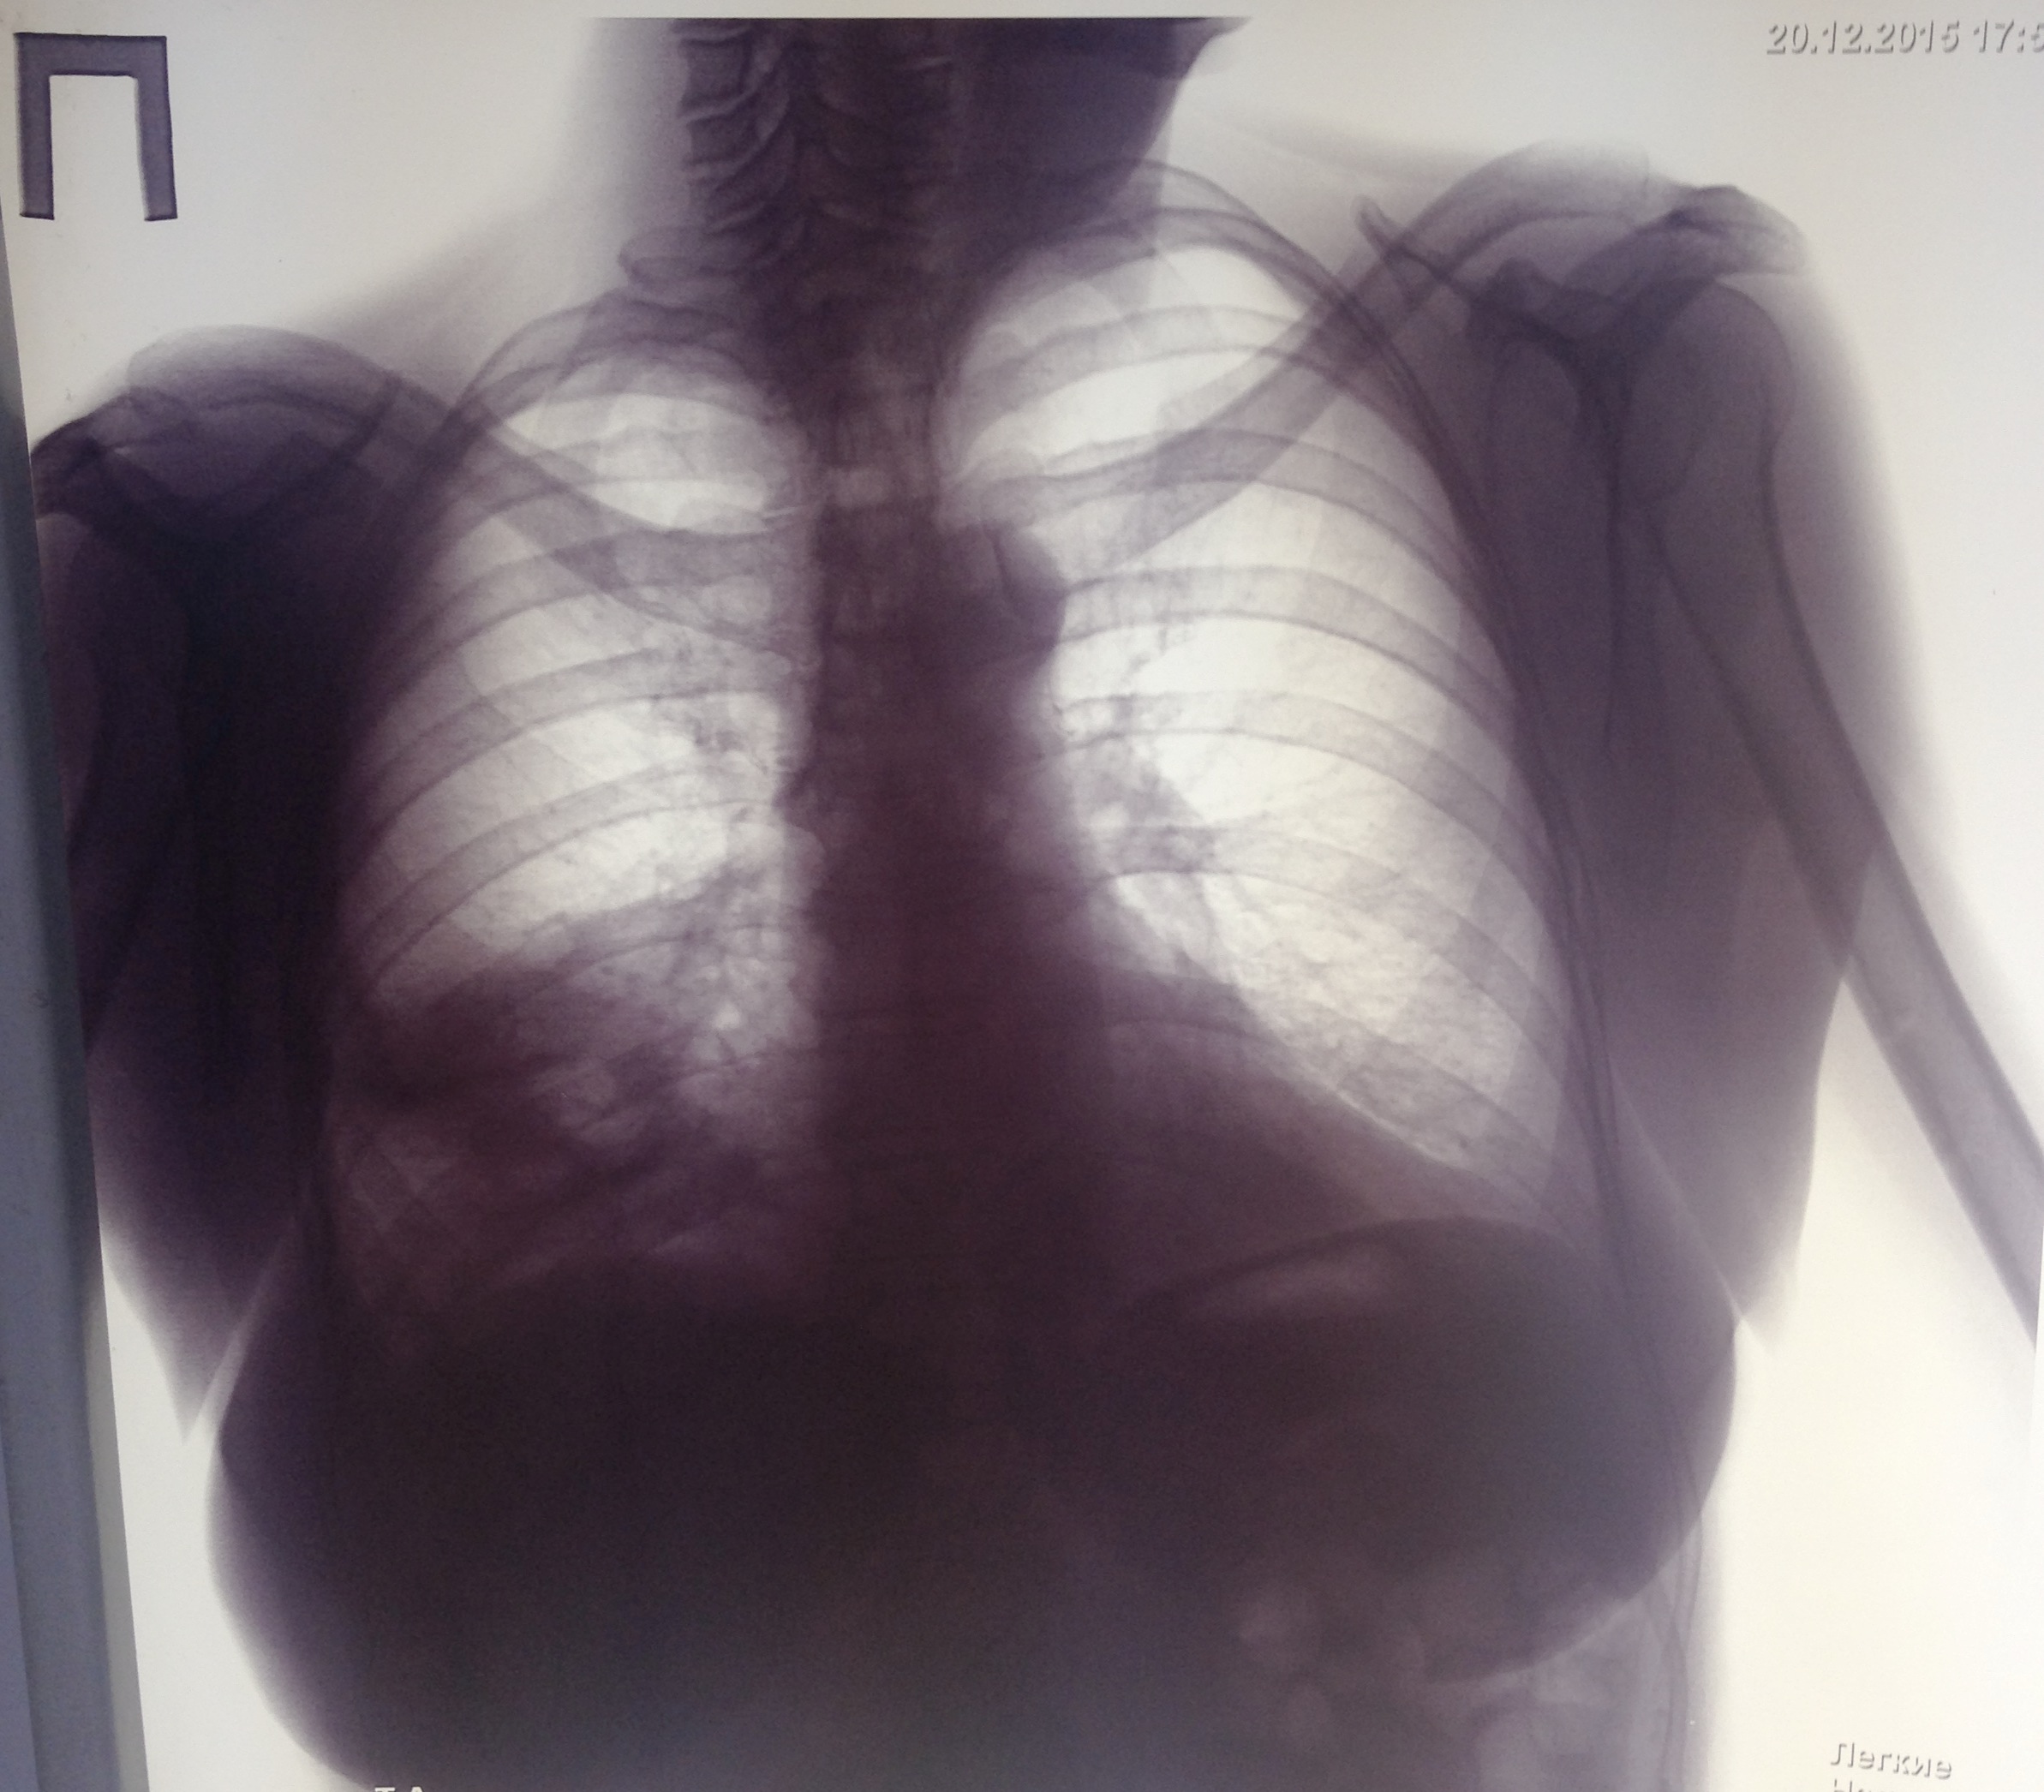

Возникновение и динамика вентилятор - ассоциированной пневмонии.

Вложения:

1-.jpg

1-.jpg [ 713.01 KiB | Просмотров: 53306 ]

2-.jpg

2-.jpg [ 759.1 KiB | Просмотров: 53306 ]

3-.jpg

3-.jpg [ 754.54 KiB | Просмотров: 53306 ]